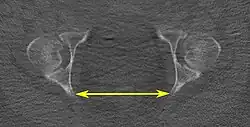

| Interspinous distance |

|

Axial plane |

The line between the closest bone points of the ischial spines | 9.5 to 11.5 cm.[6] | |